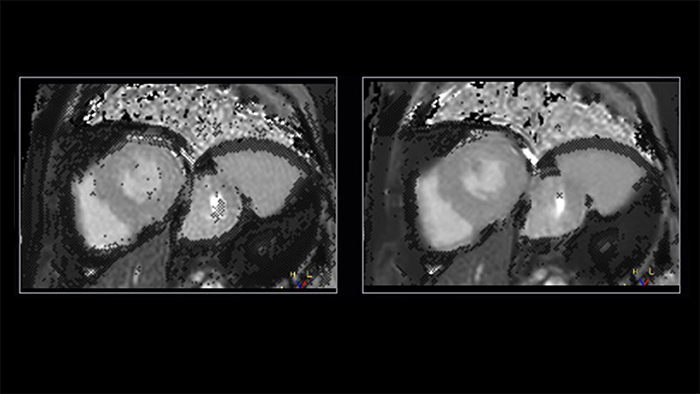

Shorter-breath holds are particularly impactful for patients who cannot manage the length of the breath-hold instruction. Mr. Strachan commented, “using Compressed SENSE sometimes pulls a non-diagnostic study into being a diagnostic study. That itself is very valuable.” For example, see Fig. 1

Figure 1. Shortening acquisition and denoising from C-SENSE provides confidence in long-axis cine of a patient with atrial fibrillation. Left to right: SENSE x2, C-SENSE x4

The impact of motion is reduced by Compressed SENSE in two ways. As well as allowing data to be acquired in a shorter duration [2] (so less movement [2] has occurred during readout), it also intrinsically includes denoising, which is a feature of any compressed sensing based acceleration method. If a motion artefact has a similar appearance to the smeared-aliasing which is deliberately produced by the incoherent undersampling which Compressed SENSE employs, the reconstruction may filter some of it out.